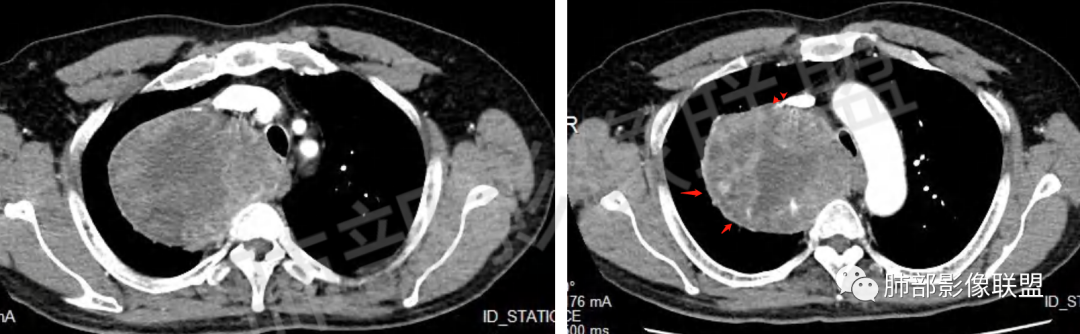

晨读病例,62岁男性,间断咳嗽四个月,影像表现右侧胸腔内见巨大肿块影,边界清晰,其内密度不均,增强扫描病灶呈不均匀性强化,病灶内见坏死及强化的小血管影,考虑恶性病变,肉瘤类病变,纤维肉瘤,滑膜肉瘤,癌肉瘤,恶性纤维组织细胞瘤。

男,62,间断咳嗽4月。胸部CT:右侧胸腔大肿块,向内压气管,向前压上腔Ⅴ,向外挤压右上肺,右上肺体积缩小,瘤肺界面清楚,交界处可见压缩带,胸膜尾可见,平扫密度不均匀,增强可见大片低密度区,AB区?考虑肺外来源,N源性肿瘤(鞘瘤)?SFT?鉴别胸腺肿瘤,肺肉瘤等。

边界清楚、光滑,D字征,与肺血管、支气管关系不密切,胸膜被掀起都提示肺外来源

上腔静脉受压前移

提示病灶来源于后方或纵隔外后方,